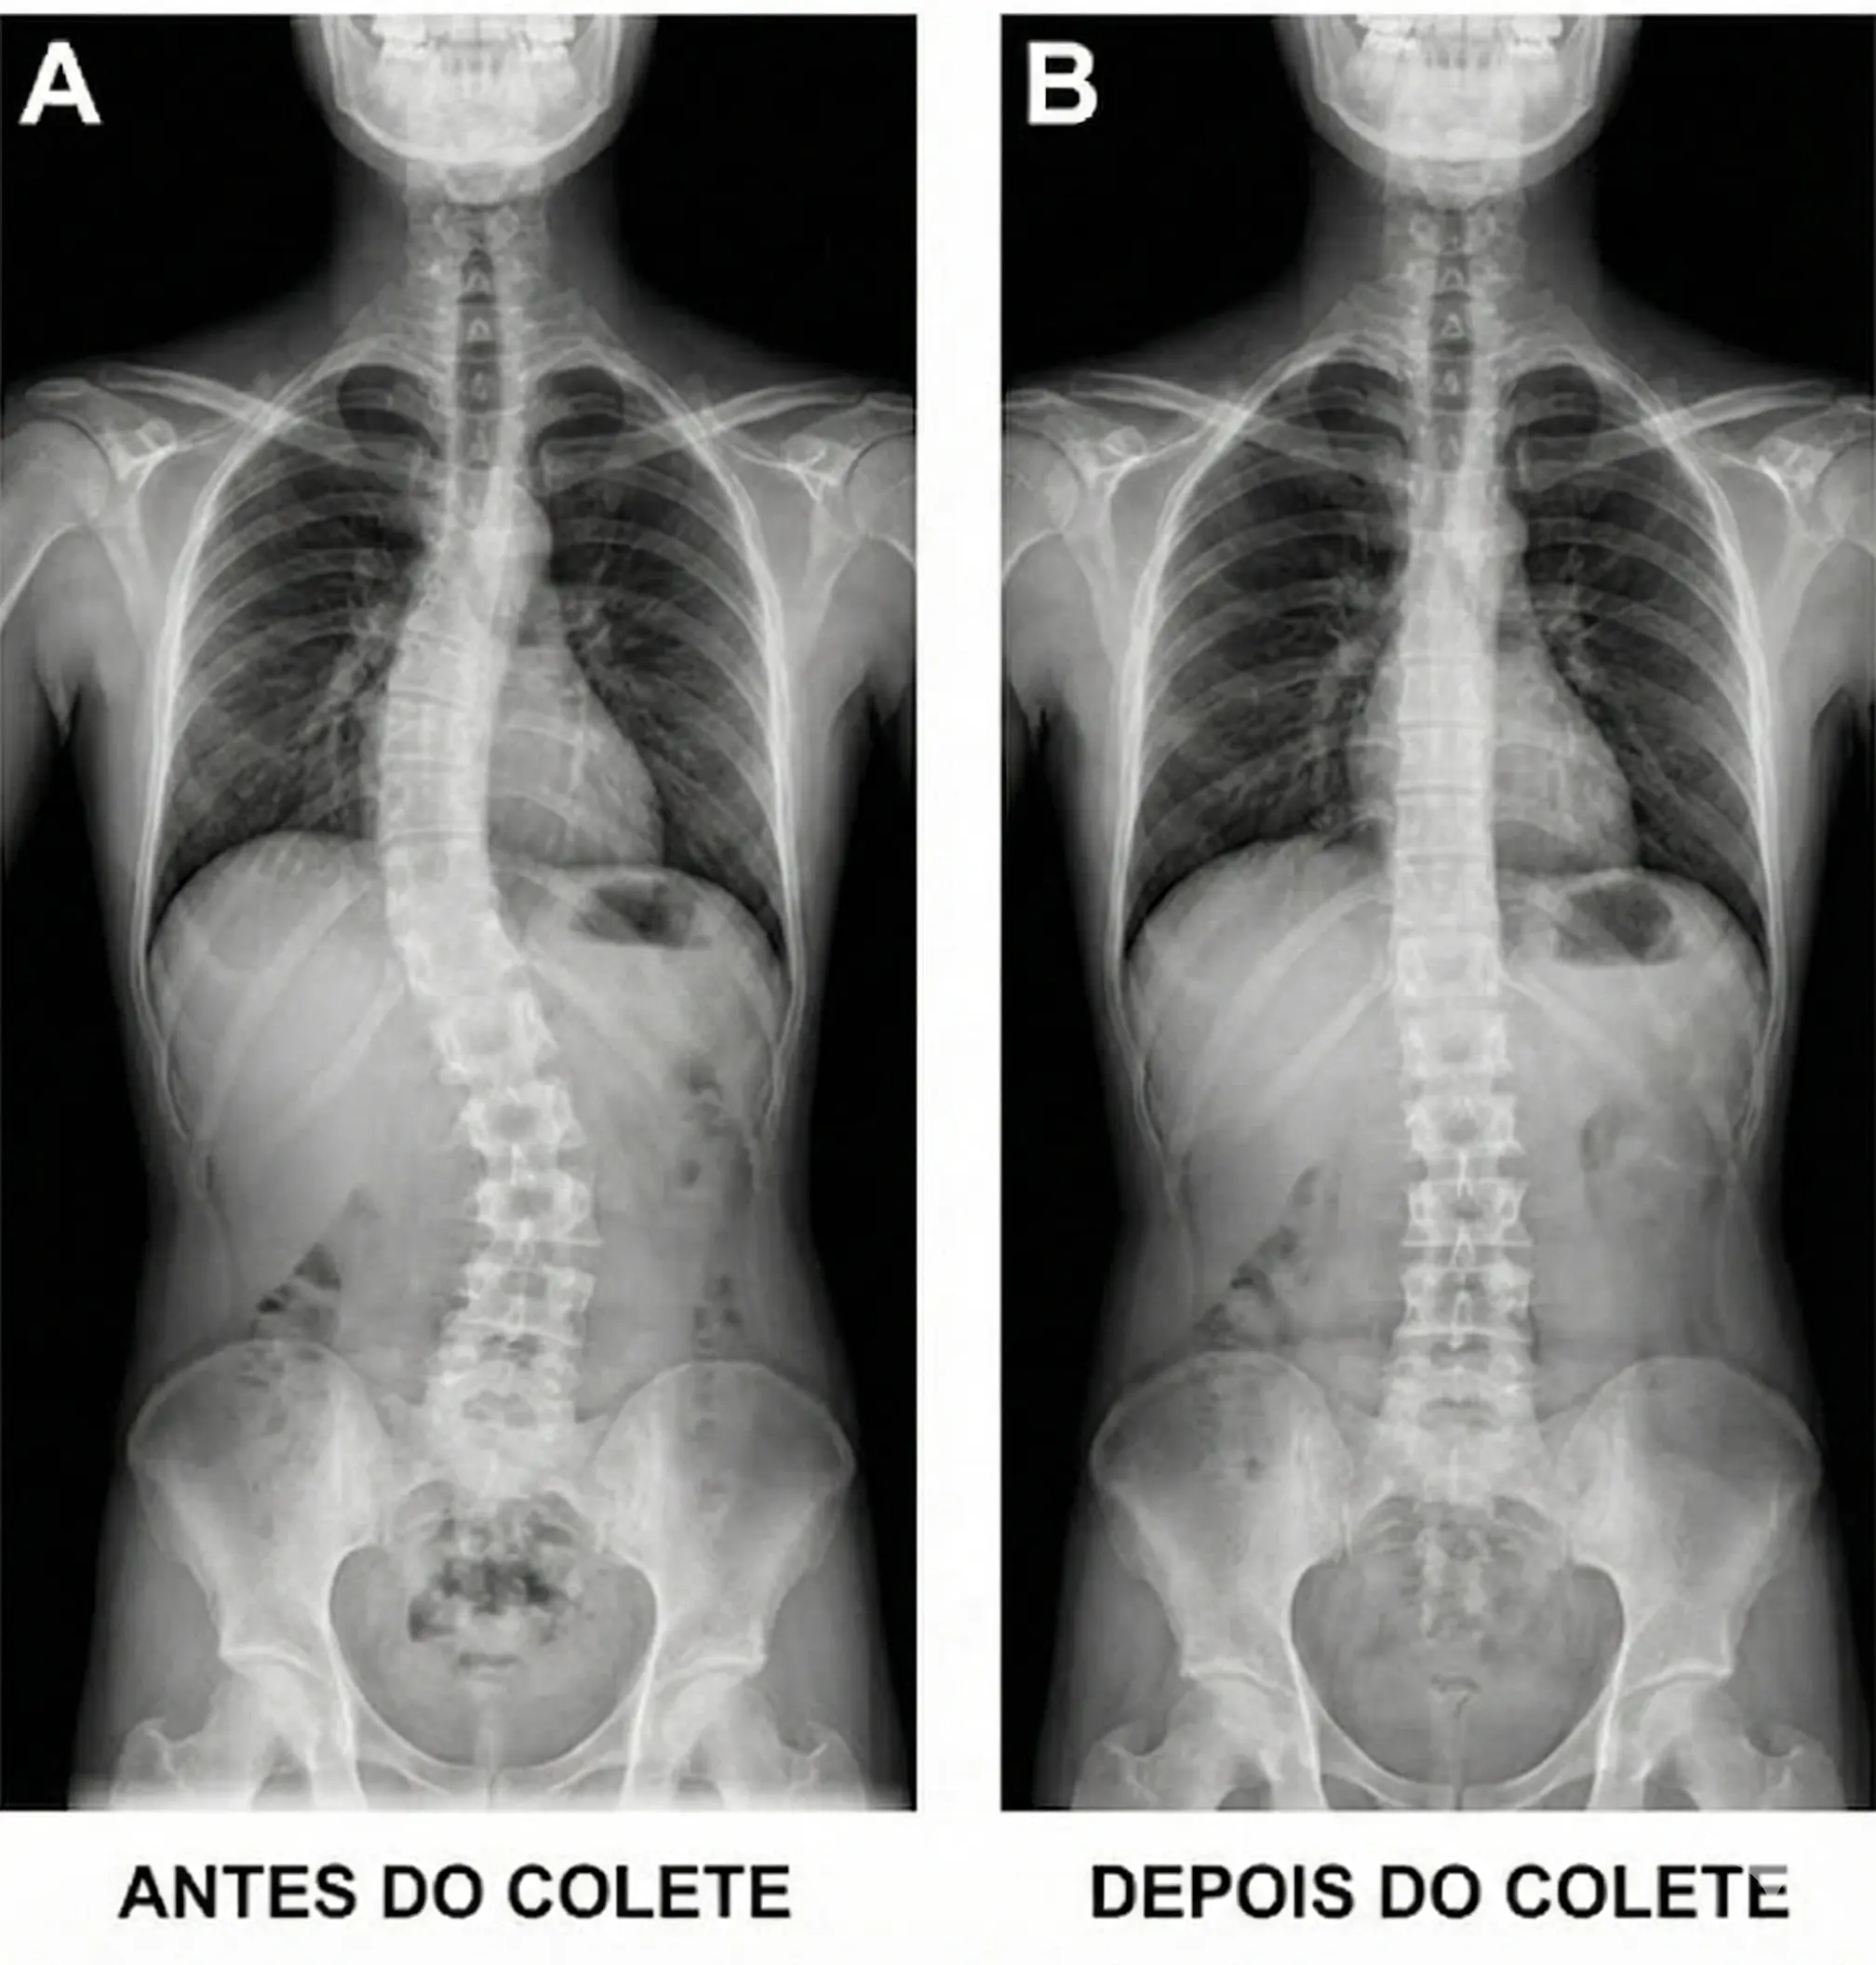

O colete funciona aplicando forças direcionais na coluna com o objetivo de reduzir a progressão da curva. Ele não corrige a escoliose de forma definitiva, mas impede que ela avance durante o crescimento.Princípios biomecânicos:

- Pressão em áreas estratégicas da caixa torácica;

- Descompressão em regiões opostas à curva;

- Estabilização enquanto a coluna cresce.

Comparativo antes/depois